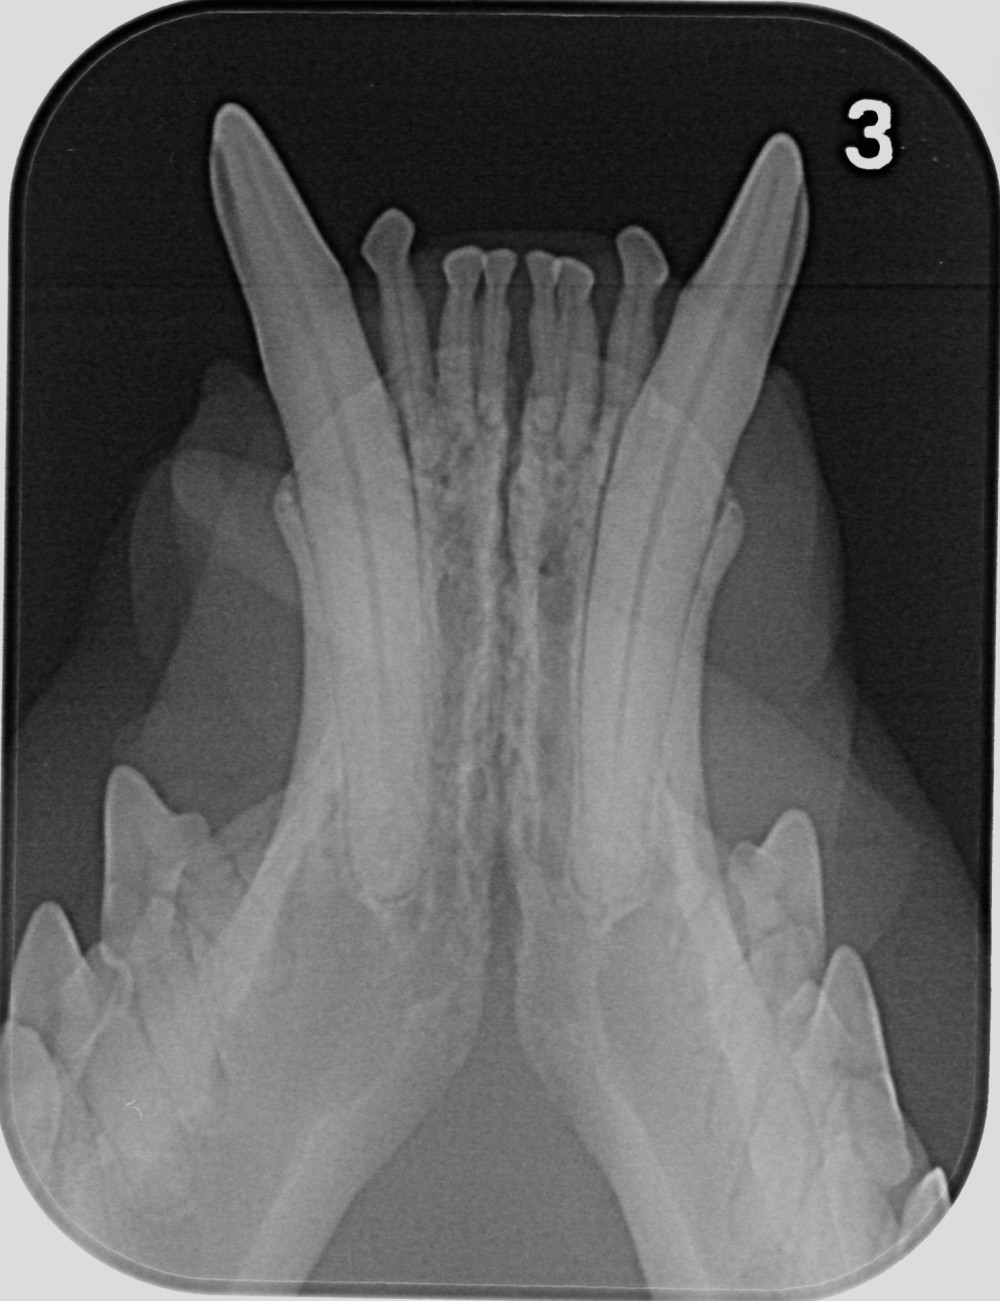

digitales Dentalröntgen: Canini UK

Zahnheilkunde

Die Gesundheit und das Wohlbefinden unserer Haustiere kann durch Zahnerkrankungen massiv gestört werden. Durch bakterielle Entzündungen, hervorgerufen von Zahnstein, Parodontose und Zahnwurzelabszesse, können dauerhafte Schäden in der Maulhöhle und den inneren Organen auftreten. Daher ist es wichtig, Ihr Tier regelmäßig auf Erkrankungen der Zähne und des Zahnhalteapparates zu untersuchen.